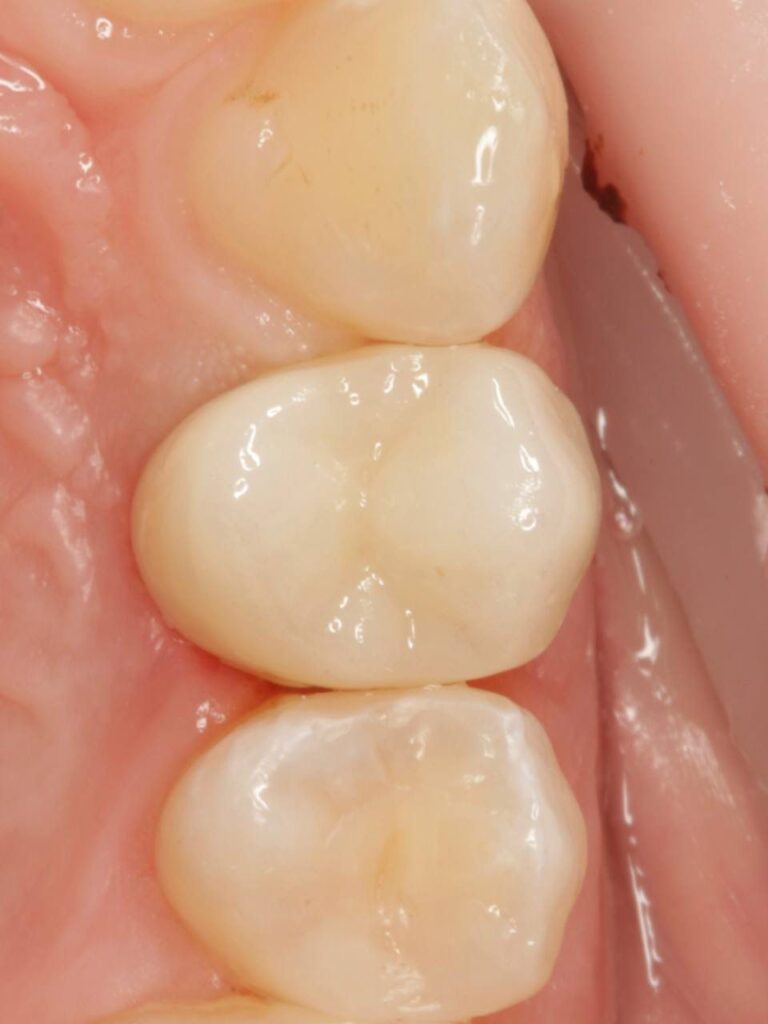

Специализация: терапия(эндодонтия), ортопедия, имплантология.